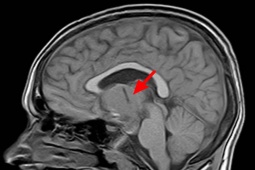

Được biết, hội chứng mông chết (DBS: dormant butt syndrome) còn được gọi là “hội chứng mông không hoạt động”. Đây là một căn bệnh làm mất chức năng cơ mông, có thể gây đau ở các khớp thắt lưng, hông và đầu gối. Khi chúng ta cần cơ mông co bóp, cơ mông dường như “quên” chức năng của mình và không thể kích hoạt được.

Các chuyên gia cho biết bệnh nhân có thể mất khả năng di chuyển khớp hông trong toàn bộ phạm vi của nó. Các cơ khác sẽ thực hiện công việc bù trừ, từ đó làm tăng áp lực lên khớp gối, lưng dưới và thậm chí cả vai, gây ra hàng loạt triệu chứng như đau lưng dưới, đau khớp háng, khớp gối.

Các chấn thương thường gặp liên quan đến "hội chứng mông chết" bao gồm hội chứng đau xương bánh chè, tình trạng đau dây chằng xương chậu, thoát vị đĩa đệm giữa và hội chứng piriformis. Việc hông tiếp tục uốn cong, các mô bị đè nén sẽ làm suy giảm và mất đi chức năng của cơ mông. Đó là lý do tại sao có thuật ngữ “mông chết” ra đời.